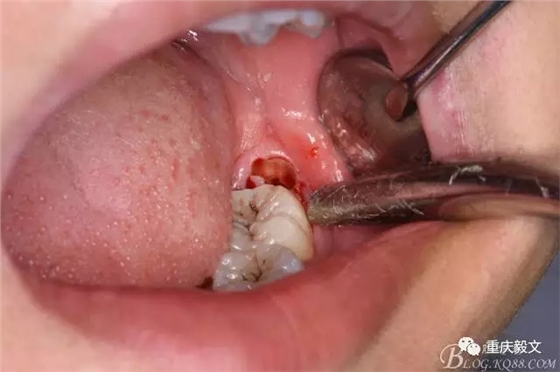

圖2.口內(nèi)可見黃豆大小大遠中面暴露,擬采用潛掘法分牙,分別取出牙冠、牙根,達到真正的微創(chuàng)拔牙